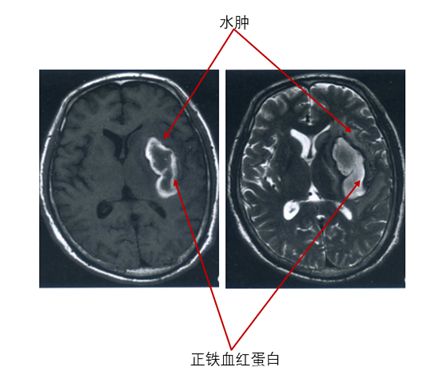

亚急性期血红蛋白的演变过程为由脱氧血红蛋白转变为高铁血红蛋白(正铁血红蛋白),这种演变由血肿外周向血肿中心部位进行。

亚急性期红细胞的演变是红细胞逐渐破裂,这一变化也是从血肿外周向血肿中心部位进行。脱氧血红蛋白的转变和红细胞的破裂可以出现重叠。当红细胞细胞膜完整时,高铁血红蛋白由于是顺磁性物质,在MRI上表现为T1高信号,T2低信号;但当红细胞溶解破裂时,如前文所述,高铁血红蛋白游离出来,血肿为低蛋白血肿液,此时MRI上表现为T1高信号,T2高信号。

在亚急性期晚期,或者说亚急性期“成熟“的时候,血肿部位的红细胞均溶解,脱氧血红蛋白均变为高铁血红蛋白,MRI上表现为T1高信号,T2低信号。亚急性期,血肿周围的水肿仍存在。